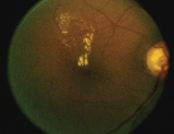

![]() 正常視網膜 |

![]() 視網膜出血、棉絮狀白點及滲出物 |

| 黃斑水腫 | |

![]() 治療前 |